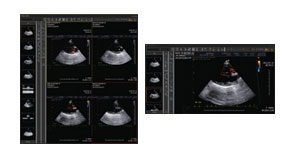

• 다중영상분할 시스템

• 독립된 PACS Viewer를 여러 번 실행할 수 있는 멀티태스킹 시스템 구축

• 한 번에 여러 환자의 영상을 비교 확인 가능